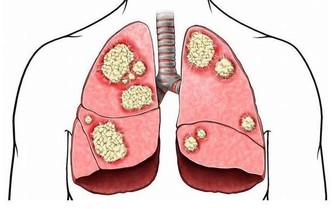

在中醫看來,白色的食物進入人體內能夠直接作用於肺部,因此對於養肺或者治療來說,白色食物不過最好。菜花是一種具有保健功效的蔬菜,既能夠預防感冒,也能起到血管清理劑的作用,因此在日常飲食中可以適量的多食用。